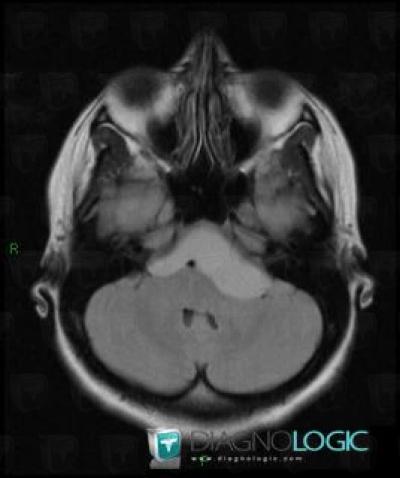

Craniopharyngiome, Angle ponto cérébelleux, IRM

Voici les informations spécifiques à l'image clé ci dessus:

- Diagnostic Craniopharyngiome, Localisation(s) Angle ponto cérébelleux, comportant les gammes Masse de l'angle ponto cérébelleux